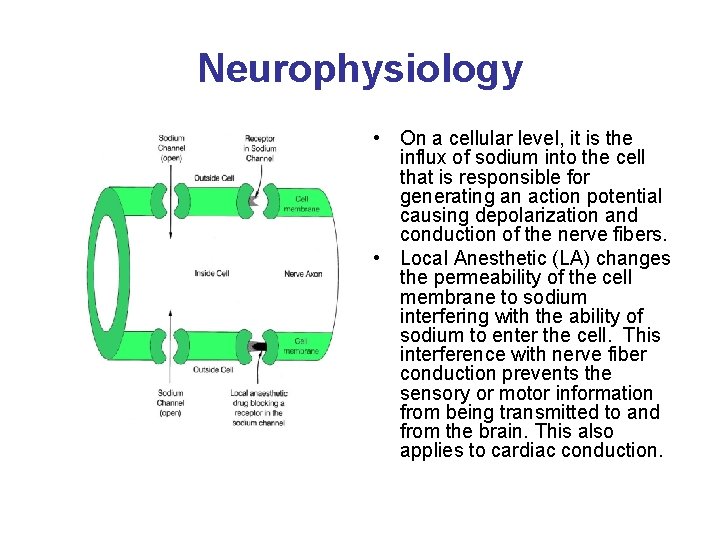

Neurophysiology • Local Anesthesia (LA) blocks transmission in ascending and descending nerve pathways. The order of the nerve fibers affected by LA is sensory, motor, and sympathetic. • Of note, resolution or regression of the block occurs first in motor fibers, then sensory and lastly sympathetic. • This pattern is important when instructing patients about preemptive pain management and postoperative use of the extremity.

Neurophysiology

Neurophysiology • On a cellular level, it is the influx of sodium into the cell that is responsible for generating an action potential causing depolarization and conduction of the nerve fibers. • Local Anesthetic (LA) changes the permeability of the cell membrane to sodium interfering with the ability of sodium to enter the cell. This interference with nerve fiber conduction prevents the sensory or motor information from being transmitted to and from the brain. This also applies to cardiac conduction.